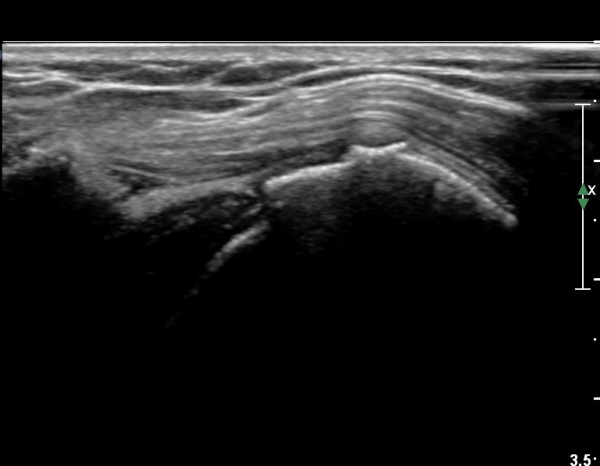

ȸÀü±Ù°³°£°Ý(rotator cuff interval) Ⱦ´Ü¸é°Ë»ç¿¡¼­ ÀÌµÎ¹Ú±Ù°Ç ¿ÜÃø¿¡ ±Ø»ó°ÇÀÌ °üÂûµÇÁö ¾Ê°í

´ë°áÀý Ç¥ÃþÀÇ »À°¡ ¿ïÅüºÒÅüÇÏ°Ô º¯ÇÏ¿´´Ù(±×¸² 1, 2)

ÀÌ´Â ½ÉÇÑ Ãæµ¹ÁõÈıºÀÇ °á°úÀ̰í ȸÀü±Ù°³ ÆÄ¿­À» °­·ÂÈ÷ ¾Ï½ÃÇÏ´Â ¼Ò°ßÀÌ´Ù.